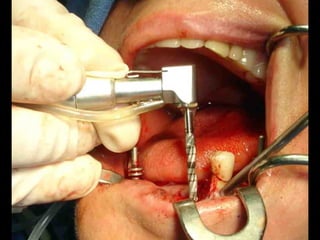

Primer tiempo quirúrgico; Exposición del maxilar para tomar una impresión del

hueso y poder elaborar la estructura implantaria.

Lingitud de hueso

Disponible 20 mm.

Implante en posición

Dejamos el implante sepultado por 4 meses previos al inicio del procedimiento

Protésico.

• Los implantes deben dejarse sin carga unLos implantes deben dejarse sin carga un

promedio aproximado de cuatro meses,promedio aproximado de cuatro meses,

después de los cuales se inicia el trabajodespués de los cuales se inicia el trabajo

protésico.protésico.

• Cuidados postoperatorios: Analgésicos,Cuidados postoperatorios: Analgésicos,

antibióticos y antiinflamatorios, hielo local lasantibióticos y antiinflamatorios, hielo local las

primeras horas y dieta licuada los 3 primerosprimeras horas y dieta licuada los 3 primeros

días.días.